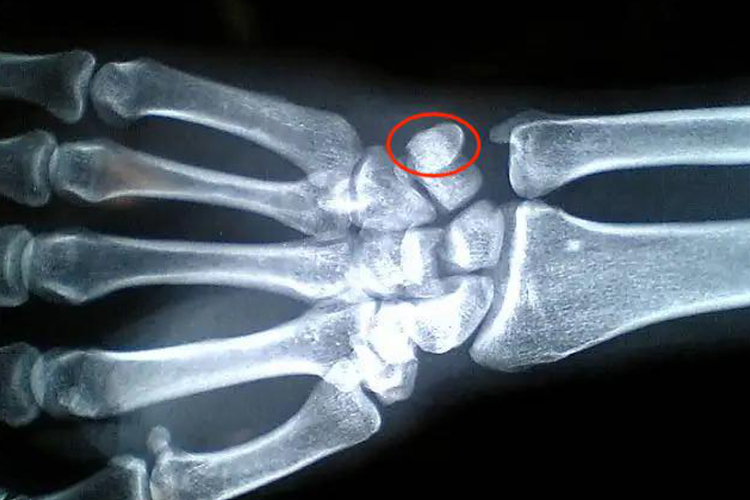

手腕豆状骨的形状像一颗豆子,疏松地与三角骨的掌面联结。

手腕豆状骨的形状像一颗豆子,疏松地与三角骨的掌面联结。豆状骨容易移动也容易触诊,它被镶嵌于尺侧腕屈肌的肌腱,具有种籽骨的特征。